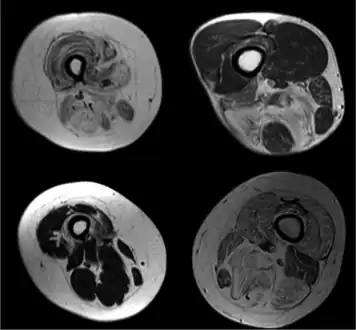

Radiologic imaging in neuromuscular disorders

Radiologic imaging in neuromuscular disorders -